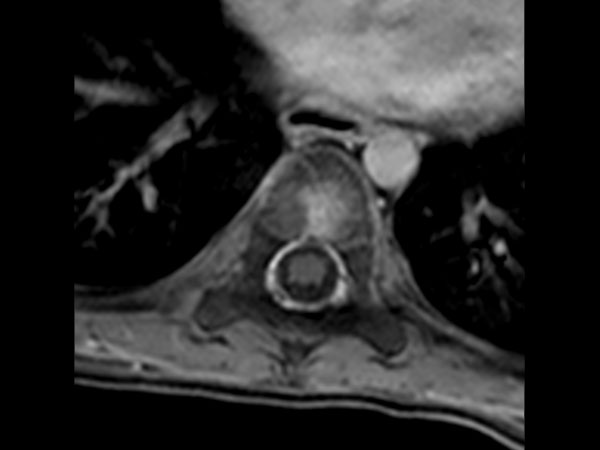

Premium Fat-free Pediatric Spine imaging

Phoenix Children Hospital, USA